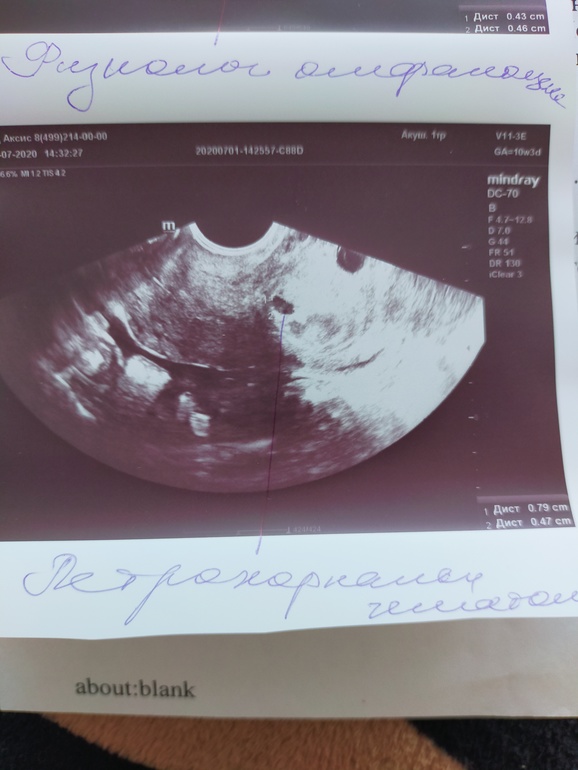

Изменения и болезни во время БВсем привет! 2 недели назад ходила на узи, с болями и бежевыми выделениями. Там у меня обнаружили гематому, ничего страшного не сказала. По размерам она небольшая. Я вычитала что гематома может рассосаться или вытечь. Она у меня получается по капле выходит, не каждый день, но вот уже 2 недели периодически бежевые выделения. Вроде маленькая, а все никак не вытечет до конца. Из-за этого боюсь ездить по неровным дорогам ( мы сейчас в отпуске у моих родителей) Сижу дома с детьми, гуляем во дворе.

Была гематома нашли 5 недель,приехала с выделениями,неделю были еще выделения ,а потом прошли,через 2 недели делала узи,гематома была,но выделений не было,сейчас 14 недель уже гематомы нет

Была тоже два раза, в в ходила коричневой мазней достаточно долго. Лежала постоянно.